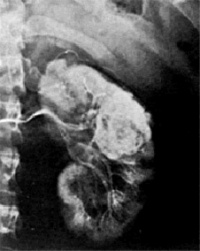

(3)肾动脉造影:肾动脉造影可发现泌尿系统造影未变形的肿瘤肾癌表现有新生血管动静脉瘘造影剂池样聚集(Pooling)包膜血管增多血管造影变异大有时肾癌可不显影如肿瘤坏死囊性变动脉栓塞等肾动脉造影必要时可向肾动脉内注入肾上腺素正常血管收缩而肿瘤血管无反应 在比较大的肾癌选择性肾动脉造影时亦可随之进行肾动脉栓塞术可减少手术中出血肾癌不能手术切除而有严重出血者可行肾动脉栓塞术作为姑息性治疗